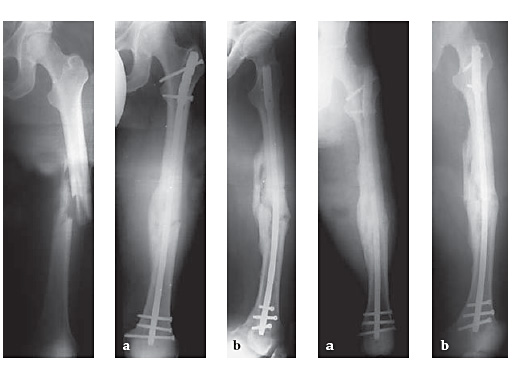

34-year-old malepolytraumatraffic accidentAO Classification 32-C3

Case provided by Hermann Bail, Berlin, DE